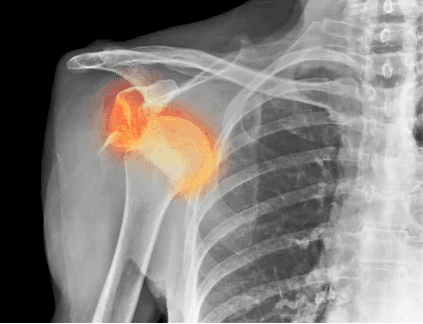

خلع الكتف هو إصابة شائعة تتسبب في خروج عظمة الذراع العلوية من تجويف الكتف.

يُعد الكتف أكثر المفاصل مرونة في جسم الإنسان، مما يجعله عرضة للإصابات مثل الخلع.

كيف يتم تشخيص خلع الكتف؟

عادةً ما يتم تشخيص خلع الكتف من خلال الفحص البدني للطبيب، وقد يطلب الطبيب تصويرًا بالأشعة السينية أو التصوير بالرنين المغناطيسي (MRI) للتأكد من وجود الخلع وتحديد مدى الضرر للأربطة أو الأوتار.